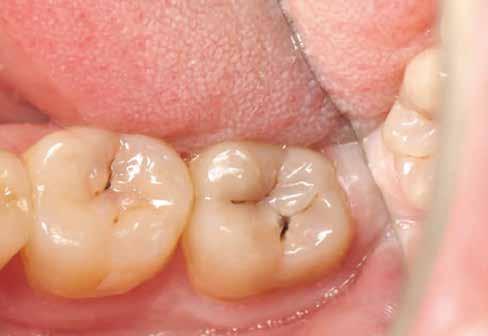

14. ábra: Egy moláris fog preoperatív állapota.

15. ábra: Egy moláris fog postoperatív fotója.